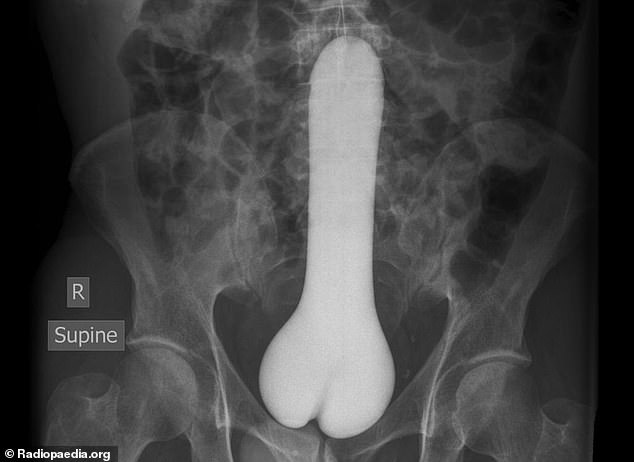

7. Ένα ερωτικό βοήθημα